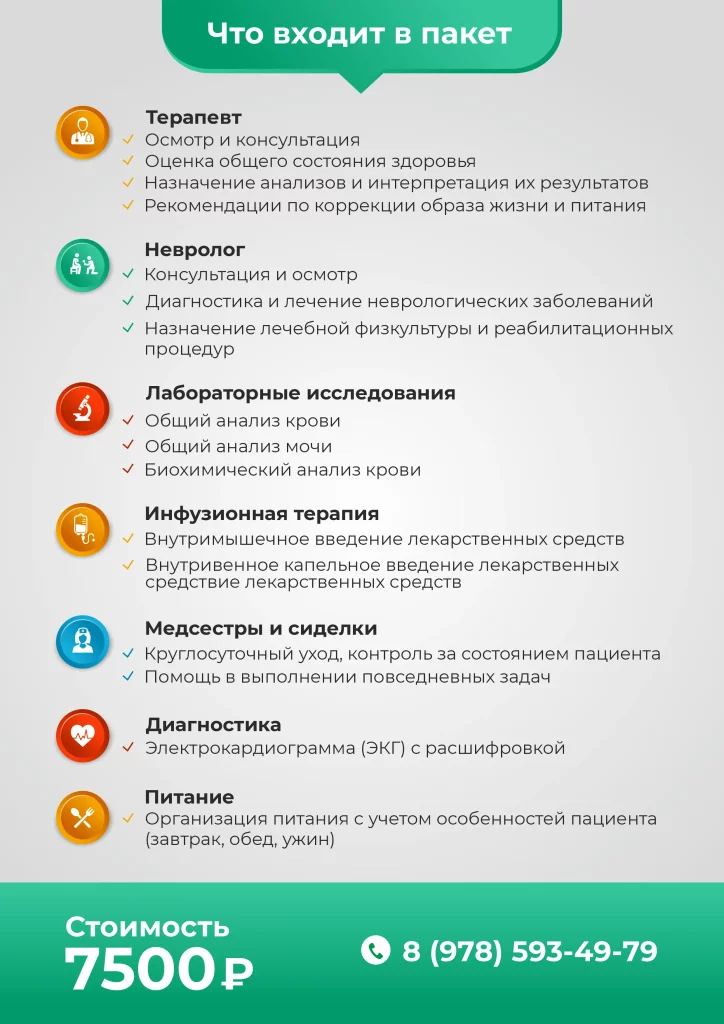

| Услуга | Стоимость |

|---|---|

| Прием врача первичный | от 2000 ₽ |

| Прием врача повторный | от 1800 ₽ |

| Прием кандидата медицинских наук первичный | от 4500 ₽ |

| Прием кандидата медицинских наук повторный | от 4000 ₽ |

| Диагностика заболевания | от 2500 ₽ |

| Взятие анализов (крови, мочи, кала и так далее) | от 1200 ₽ |

| Комплексное лечение в стационаре (цена за сутки) | от 4500 ₽ |

| Консилиум (гл.врач, психиатр, психиатр-нарколог, невролог, терапевт, психотерапевт, психолог) | от 15000 ₽ |

| Перевозка больного | от 1500 ₽ |

| Выезд врач на дом | от 8000 ₽ |